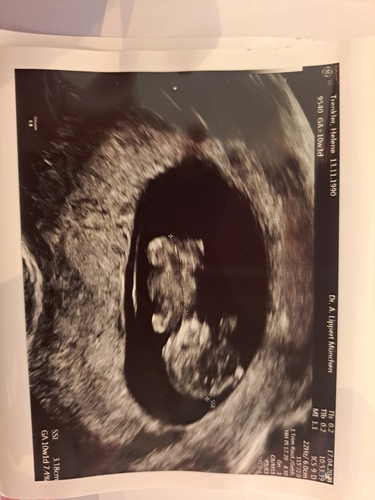

Ich war letzte Woche Mittwoch bei 10+1 da und hab ein zappeliges Würmchen gesehen und die kleinste Hand auf Erden 🥹 Freudentränen garantiert! Blut für den NIPT wurde mir auch abgenommen, das Ergebnis bekomm ich im Laufe der nächsten Woche. Meine Ärztin meinte, dass alles wirklich gut aussieht. Und das Herzchen hab ich auch gehört ♥️ hatte auch meinen Mann dabei, seitdem ist für ihn auch alles viel realer. Heute haben wir es meiner Familie gesagt, morgen ist seine dran 💕💕💕